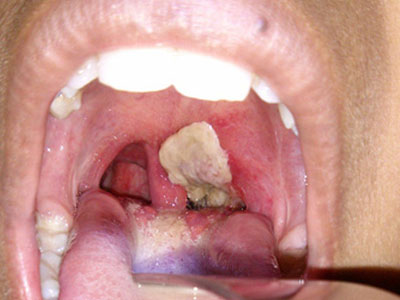

Bạch hầu: Chích ngừa đủ thì không lo!

Nếu trẻ đã được tiêm đủ các mũi 6 trong 1 hoặc 5 trong 1, phụ huynh có thể yên tâm con mình đã được miễn dịch suốt đời với bệnh bạch hầu.

17/07/2015 17:58:23